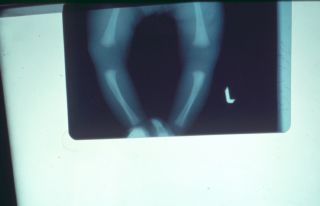

هیپو تیروئید Hypotiroid